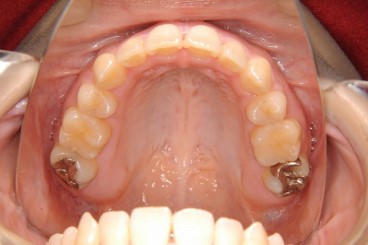

【症例】上顎前突(出っ歯)と開咬(前歯が咬み合わない)の治療

- 治療前

- 治療後

- 治療名

- 上顎前突(出っ歯)と開咬(前歯が咬み合わない)の治療

- 費用

- 検査費 40,000円(税抜) 、

治療費用 850,000円(税抜) (トータルフィー) - 期間

-

約28ヶ月(2年4ヵ月)

治療内容

患者様の症状

初診時年齢23歳の女性

上下の前歯がかみ合わないことと、歯並びのガタガタを治したいと希望して来院されました。セファロ(横顔のレントゲン)分析より、下あごの後退により上下の歯並びの前後的なずれとともに、上下的にも歯のかみ合わせが浅い(前歯のかぶさりが少ない)状態でした。さらに、歯並びからそれて生えてきた右上の小臼歯がすでに一本抜歯されていて、隙間がなくなってしまっていました。 -

治療法

左上と左右下顎の小臼歯を抜歯するとともに、すでに歯が一本少ない無い右上は、虫歯を治してある第二大臼歯を抜歯してすべての歯を後ろに下げてスペースを作ることにしました。歯科矯正用アンカースクリューというネジも支えに使って、マルチブラケット装置によりかみ合わせを整えました。

治療結果

上の奥歯の後方移動も充分に行いましたので、強い出っ歯と開咬(前歯が咬み合わない)がともにきれいに治りました。咬み合わせもしっかりと改善しています。

※治療結果は患者様によって個人差があります。

治療を行う上での 注意点 (リスク・副作用)

歯を移動する量が大きくなると、歯根吸収(根が短くなること)や歯肉退縮(歯ぐきの下がり)のリスクが高くなります。歯磨きが悪いと、歯の変色や虫歯の危険性が高くなりますが、ブラッシング状況もよく、きれいな歯が維持できました。